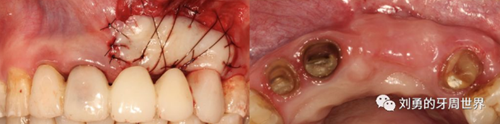

為了避免上述的問題,因此有人提出來可以將受區(qū)制備成全厚瓣,這樣將來齦瓣直接放在骨面,就不會有那些可移動纖維的存在了,術(shù)后齦瓣更加穩(wěn)定。

比如下圖:

但是該方法有個弊端,那就是受區(qū)沒有骨膜了,齦瓣的血供會變差,有人提出來了改良的方法,就是保留骨膜,但是為了減少骨膜上纖維的移動性,對骨膜進(jìn)行垂直向的全厚層切透,減少骨膜的動度,這就是垂直骨開裂的改良方法,如下圖:

還有人提出來的改良方法是在半厚瓣骨膜床的根尖區(qū)域做全厚層切口,離斷來自根向的肌肉纖維或系帶的牽拉,該方法稱之為骨膜分離的方法,如下圖: